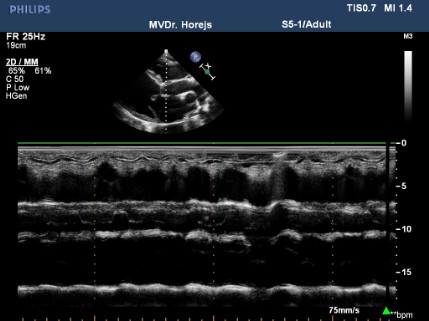

Dilatační kardiomyopatie